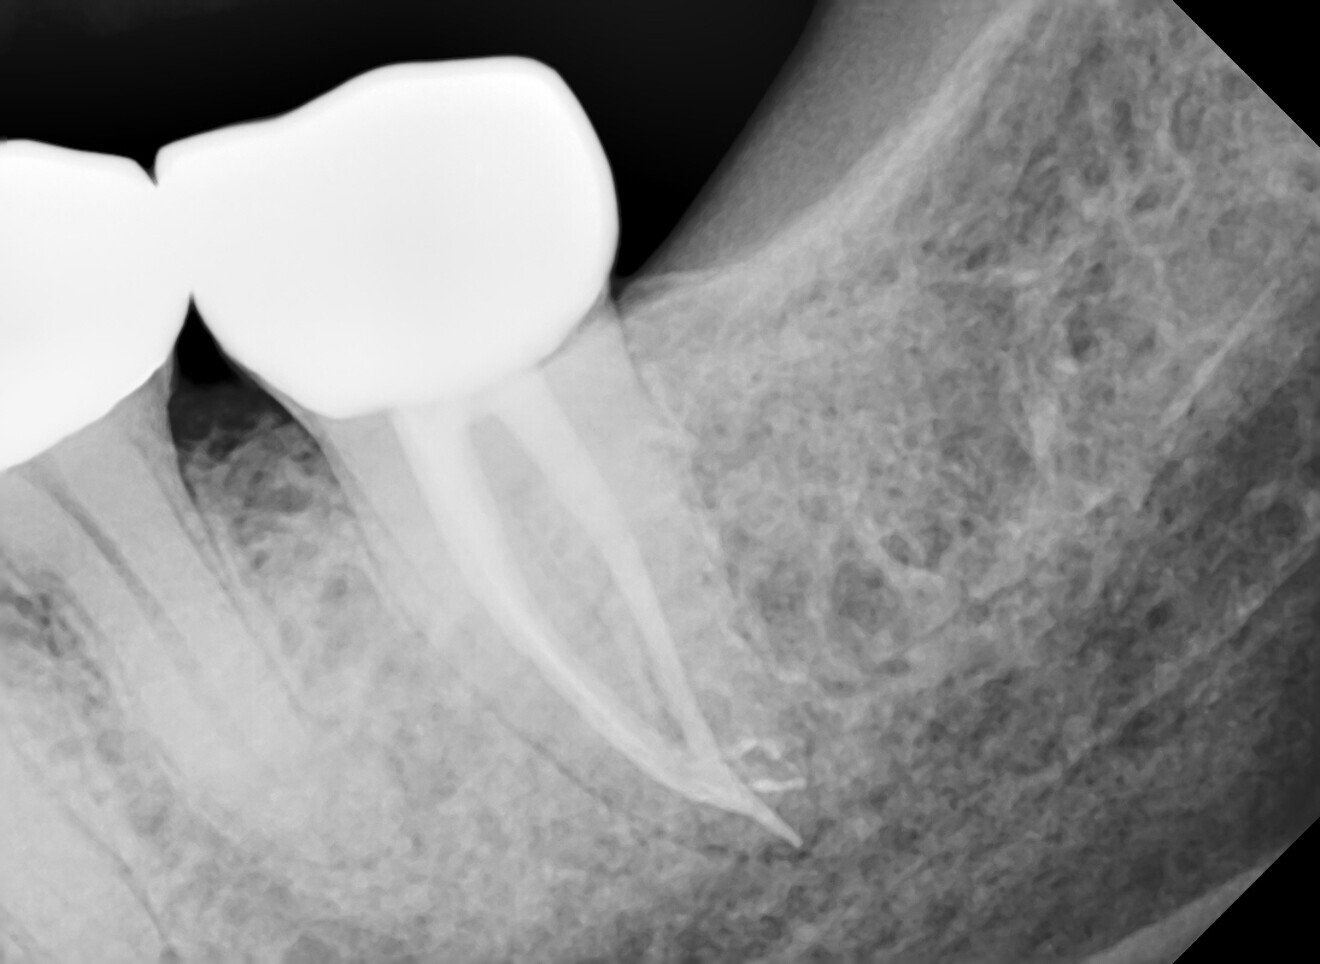

During a 30-second resting phase, the irrigant within the pulp chamber appeared to become cloudy. Number 10 files were placed in all the three canals until resistance was met, and all were restricted from passing 18 mm. A working length radiograph was taken (Fig. 2), and it showed that the files in the mesial canals had reached a point of constriction or obstruction which would not allow further access towards the apex. After a further five cycles of laser-assisted irrigation with 17% EDTA with a 30-second resting time and recapitulation with #10 and 15 files, the instruments were able to reach the apex at 22 mm in the distal canal and 21 mm in the mesiobuccal and mesiolingual canals (Fig. 3). This showed that the irrigant had successfully penetrated the canal system and dissolved the blockage that had prevented initial access to the apical segment. After the canals had been prepared with rotary files, the final irrigation protocol was done, initially allowing more cloudy liquid to float to the surface. At the completion of laser-assisted irrigation, the canals were dried with paper points, and no bleeding was observed.

Fig. 2.